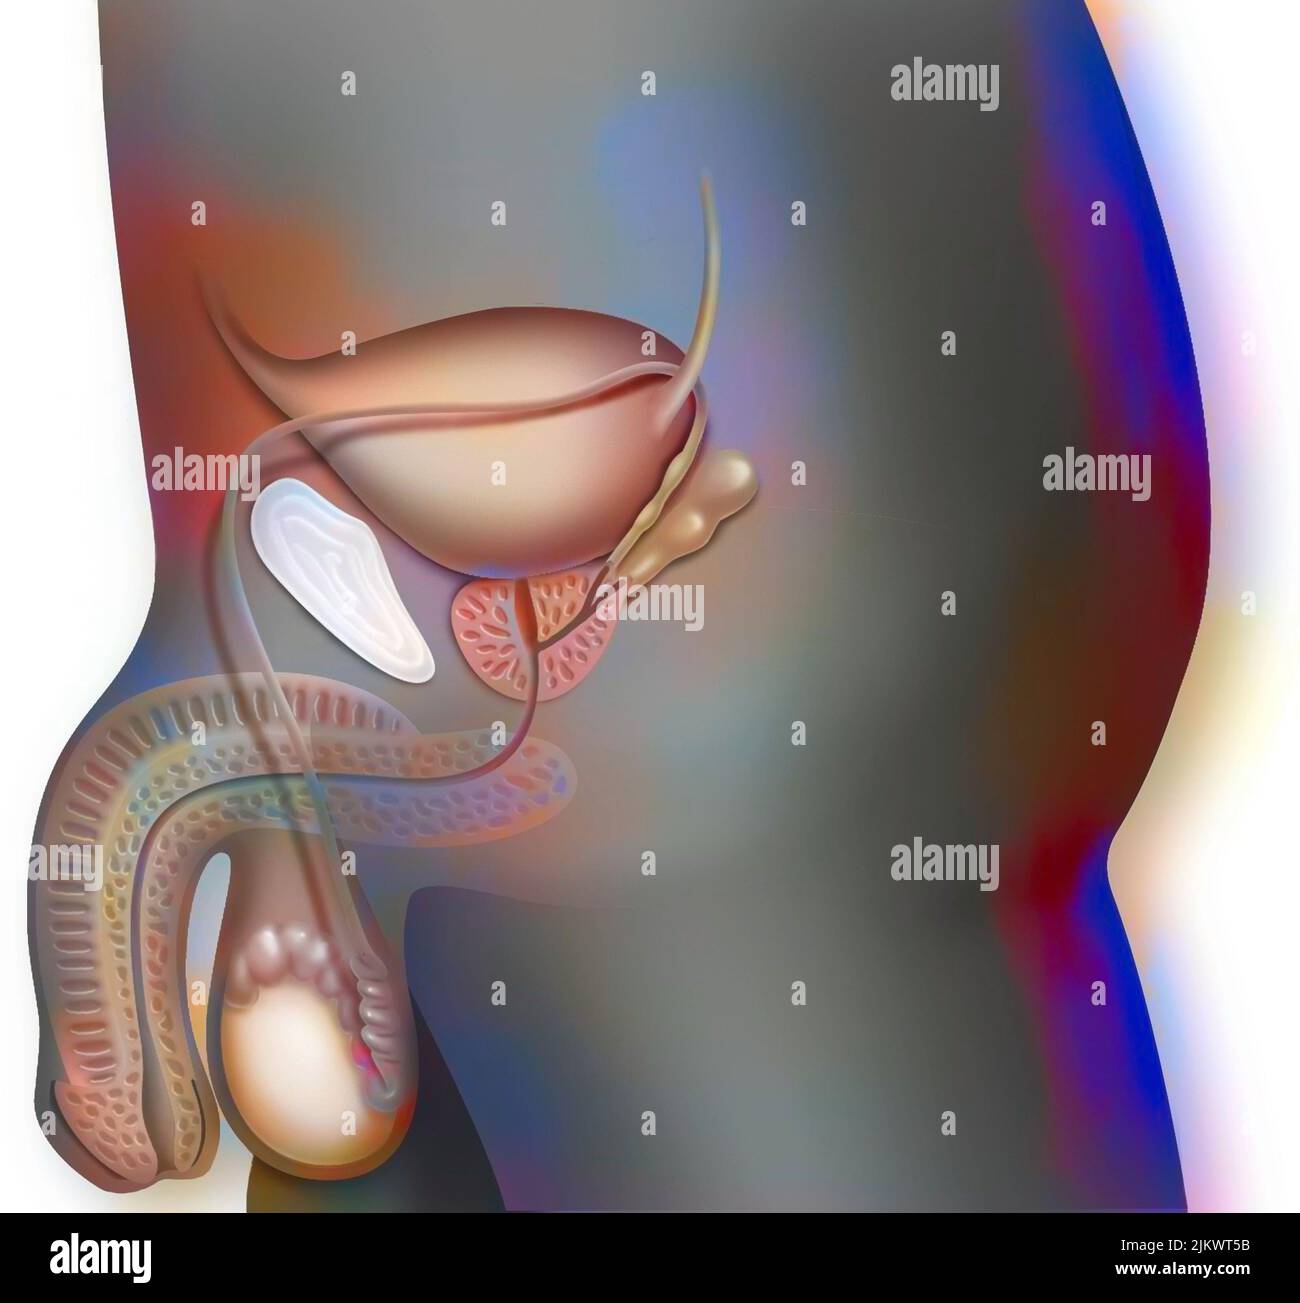

RF2JKWRM1–Vue antérieure des organes génitaux féminins avec vagin, utérus, trompes de Fallope, ovaires.